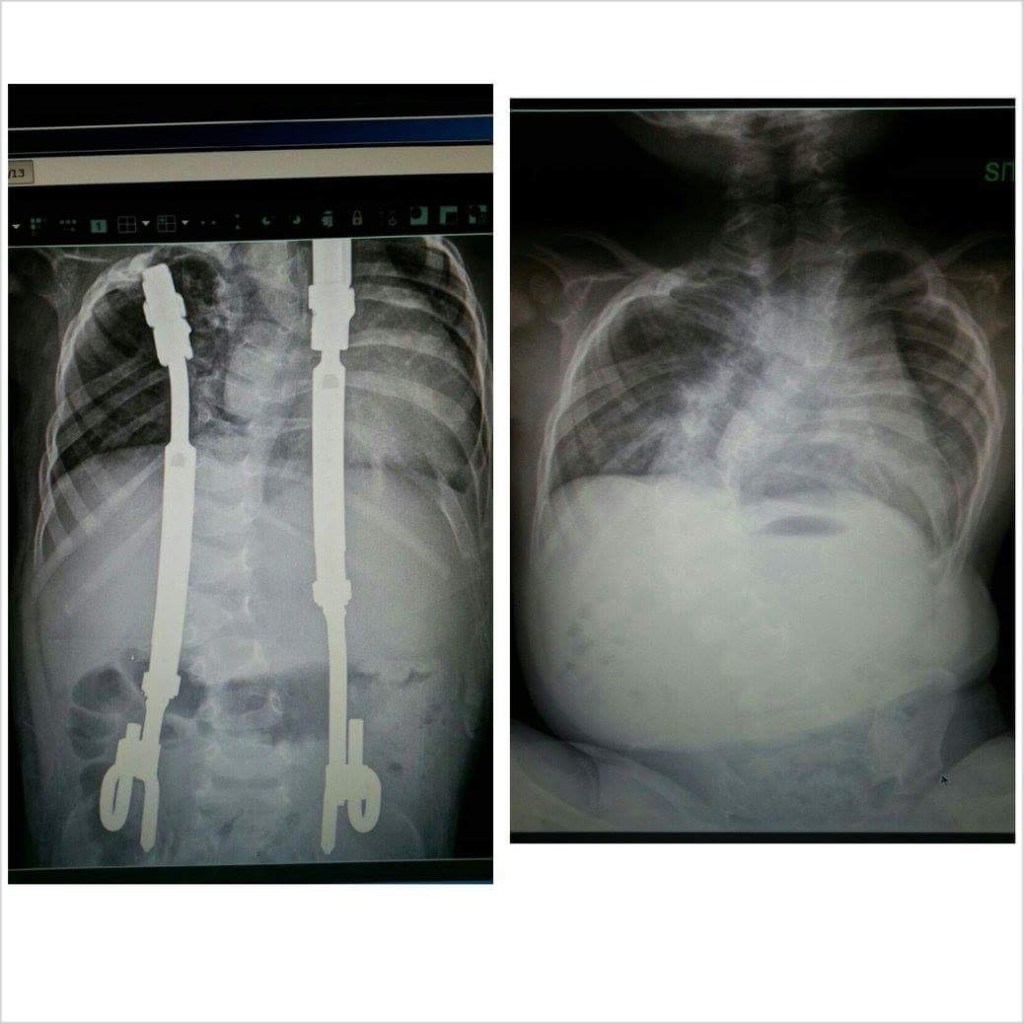

Traditional Growing Rods (TGR):

TGR attach below and above the spinal curve.

Vertical Expandable Prosthetic Titanium Rib (VEPTR):

The Vertical Expandable Prosthetic Titanium Rib is a curved metal rod surgically attached to a child’s rib, spine, or pelvis using hooks on both ends. VEPTR’s separate the rib and straighten the spine, allowing their lungs to grow with the child.

MAGnetic Expansion Control System (MAGEC):

The MAGnetic Expansion Control System includes implantable rods that allow non-invasive expansions. However, young children with severe or stiff spinal deformities do not benefit from MAGEC rods. Ultimately, surgeons rarely perform conversion operations (removing TGR/VEPTR and exchanging with MAGEC) due to the magnetic growing rods not being strong enough.